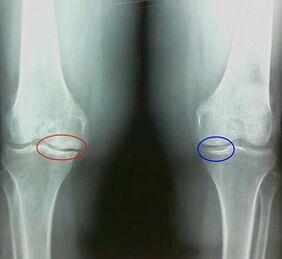

For example, what is the difference between arthritis and arthritis of the knee joint?With arthritis, the synovial shell of articular tissue occurs.This causes an increase in temperature in the joint.

Common shirts, a continuous pain syndrome develops, intensifying during movement.With arthritis, the pain occurs only after physical activity, you can hear a characteristic crisis or clicks on the joint, gradually the fusion is deformed and loses mobility.